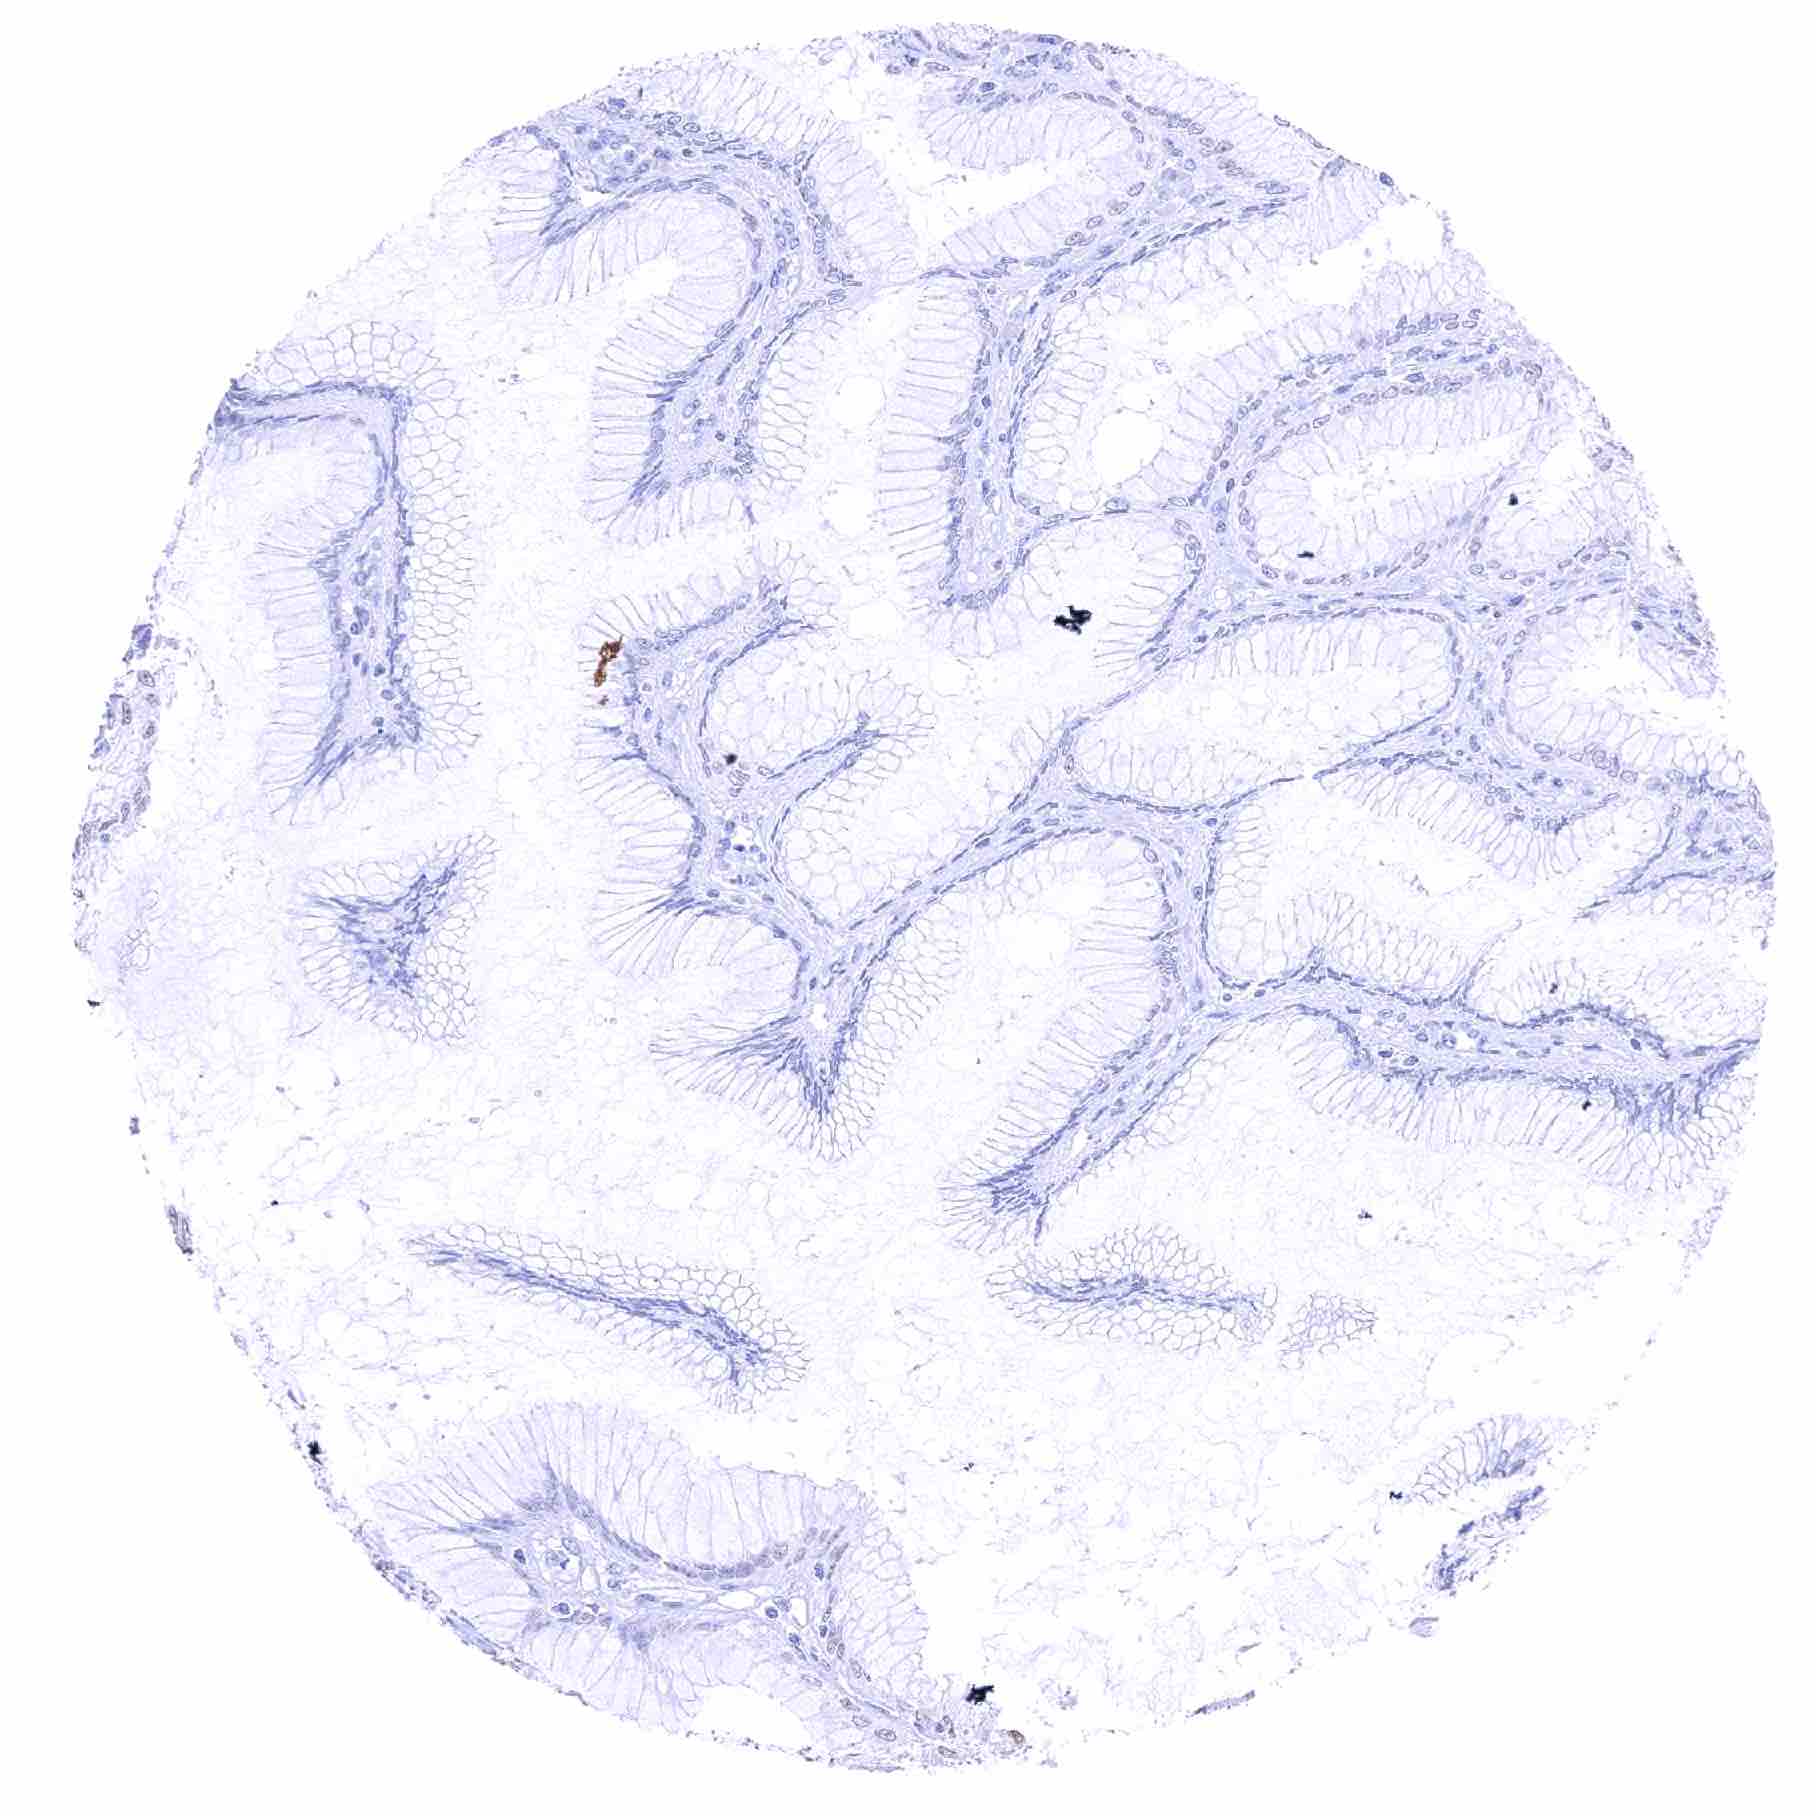

Colon descendens, mucosa